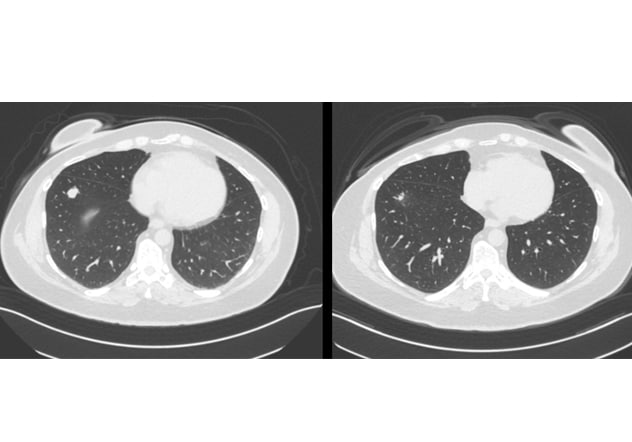

Lung lesion

The scan on the left shows a pre-redifferentiation right lung lesion. The scan on the right shows the same lesion six months after redifferentiation plus radioactive iodine, demonstrating a significant structural response.